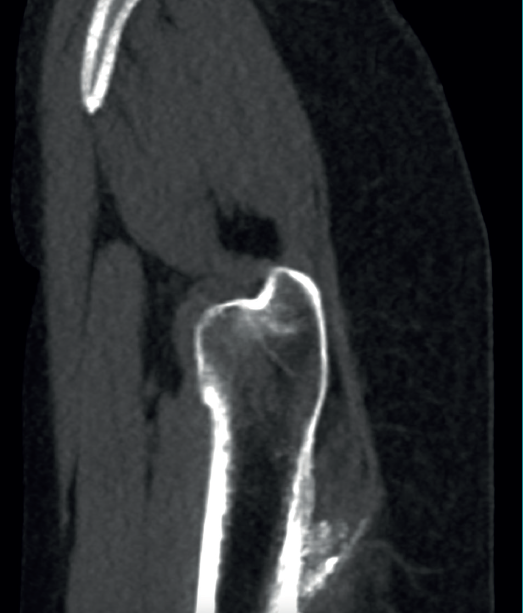

The physical examination revealed a limp-free gait and complete joint balance, with no positive signs of femoroacetabular impingement or inguinal pain. Muscle strength was preserved and similar to that of the contralateral side. She experienced intense pain on palpation of the insertion of the gluteus maximus, referred proximally to the ipsilateral buttock. The pain was reproduced on extension against resistance, and prevented sitting for long periods. Plain radiographic and computed tomography (CT) images revealed calcific tendinosis affecting the aponeurotic prolongation of the gluteus maximus in proximity to its insertion in the upper region of the linea aspera of the femur (Figures 1 and 2) Magnetic resonance imaging (MRI) of the hip showed a labral tear, that proved asymptomatic in the physical examination. In view of the clinical picture of radicular pain, an MRI scan of the lumbar spine and subgluteal space was also performed, ruling out radicular involvement or sciatic neuritis. Her previous treatment over the three years of evolution of the disorder included oral nonsteroidal anti-inflammatory drugs, a specific physiotherapy programme and several ultrasound-guided corticosteroid injections with positive results - though a last session showed no response. Due to the severity and chronicity of the symptoms and their resistance to conservative treatment, surgery was decided to clean and remove the intratendon calcification endoscopically.

In cases of calcific tendinopathy of the gluteus maximus, calcifications in the femoral metaphysis can be seen on plain radiographs, though a normal image may also be seen. Therefore, CT and/or MRI scans are usually necessary for establishing the diagnosis, exhibiting an irregularity or cortical erosion at the insertion of the gluteus maximus in the gluteal tuberosity, located on the posterolateral surface of the femur, distal to the greater trochanter, accompanied by areas of tendon calcification, local inflammatory signs and, in some cases, partial intratendinous ruptures(17). Use can also be made of CT-guided single-photon emission computed tomography (SPECT-CT), which pinpoints the anatomical location and assesses the activity of the lesion, and is of interest in the differential diagnosis in oncological patients(18).